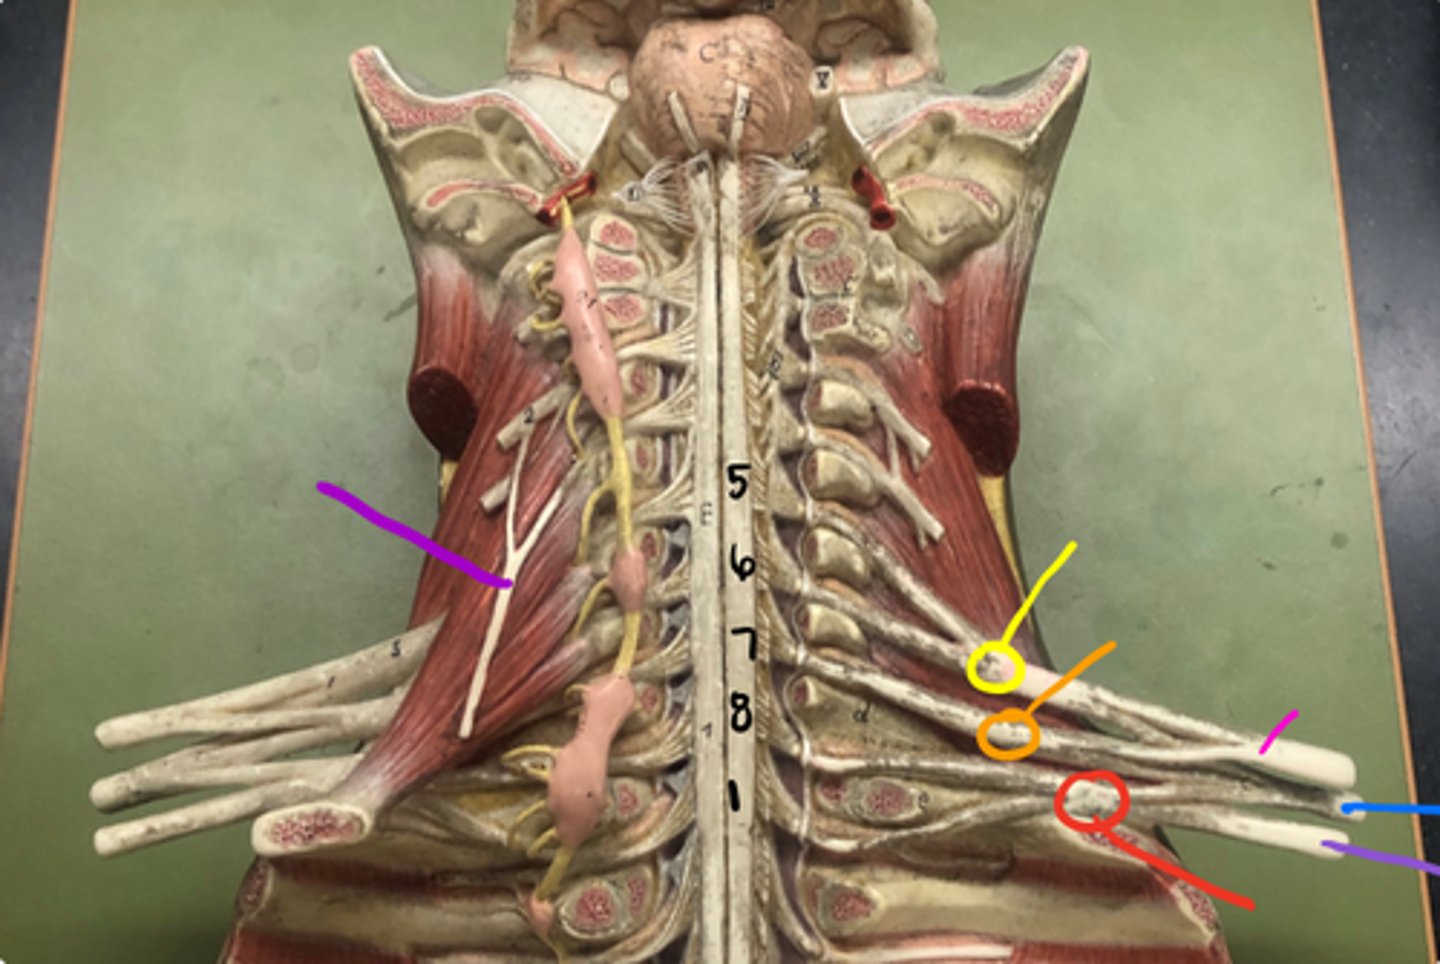

posterior root

axons of sensory neurons

posterior root ganglion

anterior root

axons of motor neurons

spinal nerve

cauda equina

bundle

cervical plexus

C1-C5

brachial plexus

C5-T1

lumbar plexus

T12- L4

sacral plexus

L4- S4

phrenic nerve

neon purple (on neck)

superior trunk

yellow

middle trunk

orange

inferior trunk

red

lateral cord

pink

medial cord

purple

posterior cord

blue